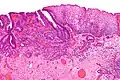

Esophageal cancer Micrograph showing histopathological appearance of an esophageal adenocarcinoma (dark blue – upper-left of image) and normal squamous epithelium (upper-right of image) at H&E staining

Micrograph showing histopathological appearance of an esophageal adenocarcinoma (dark blue – upper-left of image) and normal squamous epithelium (upper-right of image) at H&E staining